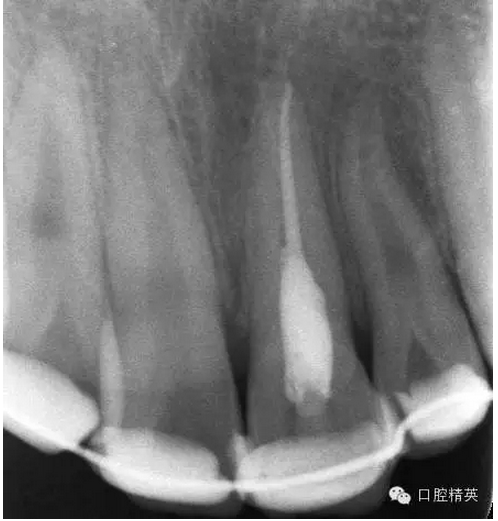

x線(xiàn)檢查:21牙槽窩空虛,窩內(nèi)未見(jiàn)其他遺留物。

圖3.患者21根尖片,牙槽窩空虛,無(wú)變形。

圖18.復(fù)位臨時(shí)固定后的x線(xiàn)根尖片。患者牙根與牙槽窩吻合。

圖23.樹(shù)脂+牙弓夾板固定完成后的x線(xiàn)片影像

圖5.拆除樹(shù)脂夾板前的x線(xiàn)根尖片影像,21根尖出現(xiàn)少許吸收。大家擔(dān)心的情況出現(xiàn)了。